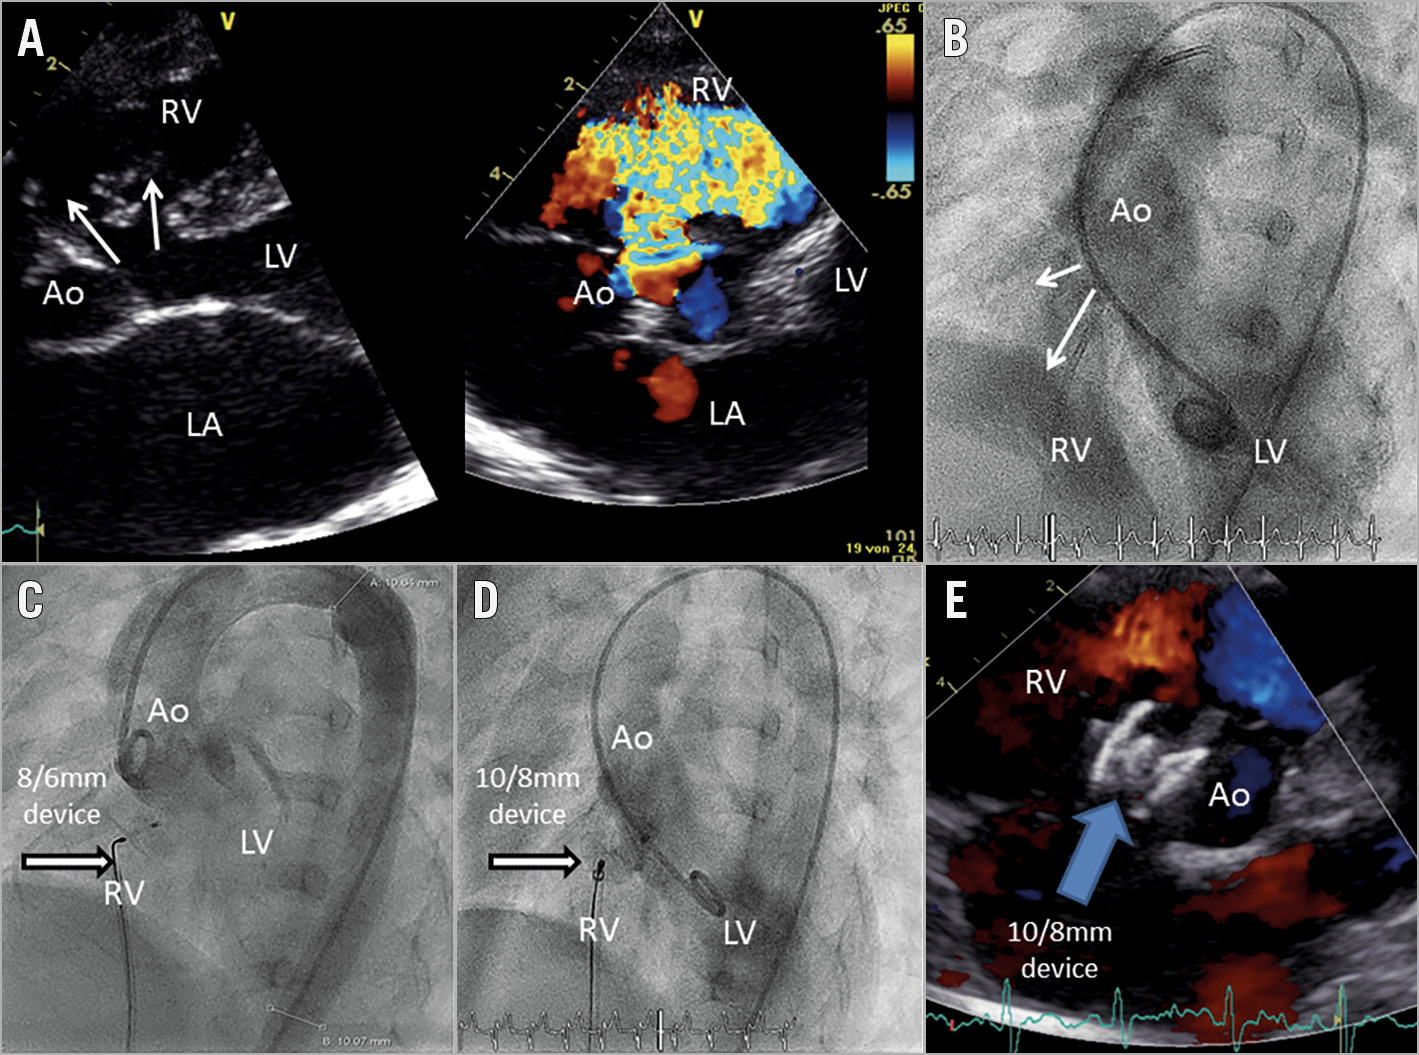

From eurointervention.pcronline.com

First European experience of percutaneous closure of ventricular septal Residual Shunt After Vsd Closure principally, residual shunts after surgical closure of vsd are not uncommon, ranging from 5 to 25%,. we evaluated our results in the current era after surgical closure of a vsd with regard to residual defects and. the findings of the present study revealed that the closure of vsd residual shunts with on beating heart. the amplatzer. Residual Shunt After Vsd Closure.